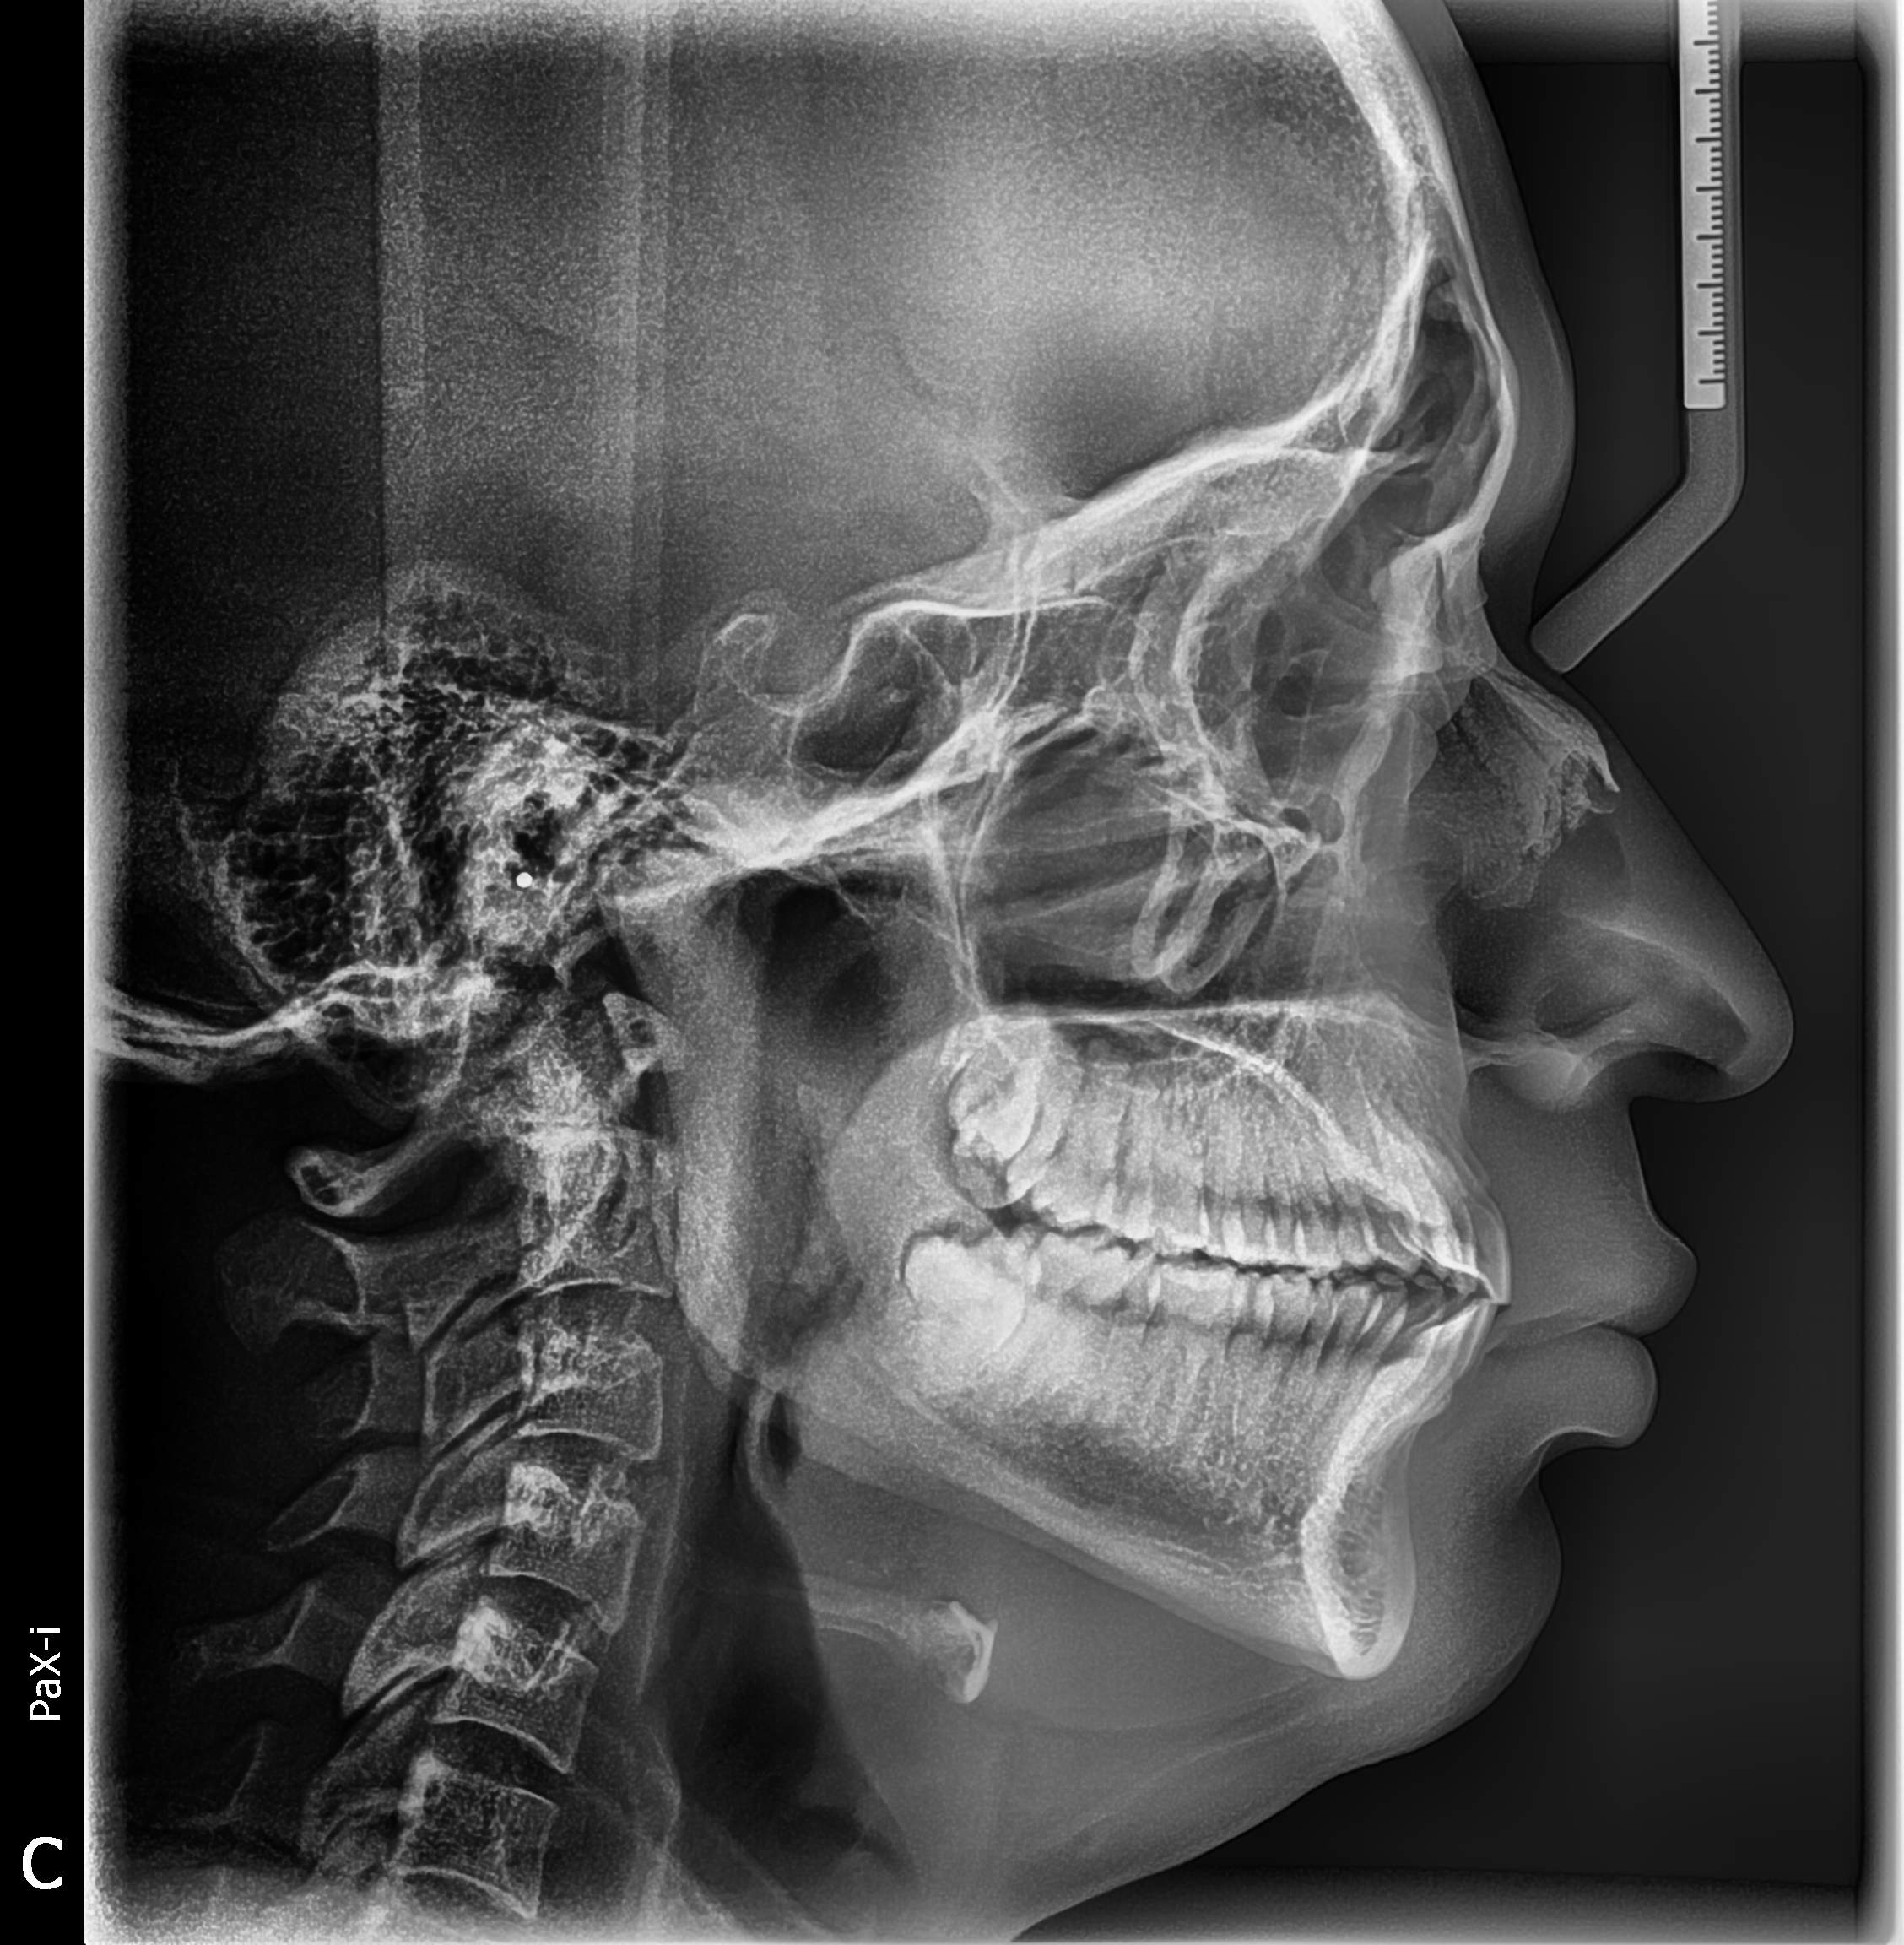

Gracias al Dr. Fernando Peña , por seguir confiando en nosotros y adquirir su nuevo equipo. Centro ubicado en Villa el Salvador - Lima, instalación de equipo PaX-i SC (Panorámico/Cefalometrico) de la marca VATECH.